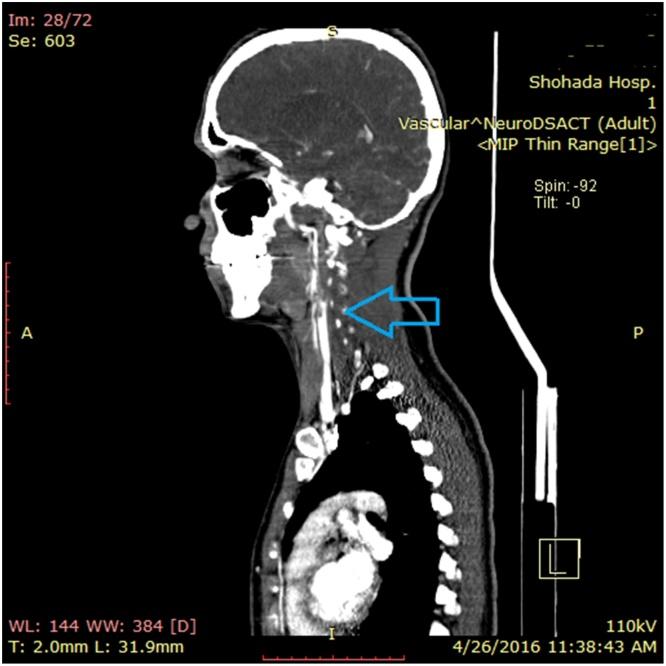

Carotid free-floating thrombus causing stroke in a young woman with lupus anticoagulant: A case report and review of the literature.

A-25-year old woman was referred to hospital with sudden onset aphasia and right sided hemiparesis. Carotid duplex ultrasonography showed an iso-echogenic thrombus ranged about 5×10mm partially attached to arterial wall of the right internal carotid artery. It was floating in accordance with the heartbeat. Anticoagulation therapy was initiated and subsequently she underwent an urgent operation. To explore the etiology of her problem, various lab tests were carried out; the results showed markedly elevated levels of lupus anticoagulant. She was discharged from hospital after an uneventful recovery showing gradual improvement of symptoms in follow-up visits.

一名25岁女性因突然出现失语和右侧偏瘫被转诊至医院。颈动脉双功超声检查显示,一个大小约为5×10mm的等回声血栓部分附着于右侧颈内动脉的动脉壁上。它随心跳浮动。开始进行抗凝治疗,随后她接受了紧急手术。为探究其问题的病因,进行了各种实验室检查;结果显示狼疮抗凝物水平显著升高。她在顺利康复后出院,随访中症状逐渐改善。